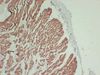

Actin Mouse Monoclonal Antibody [Clone ID: 8B10-3F7-1B8] TA385598 USD 380.00 4 Weeks Sacomeric Muscle Actin (8B10) Mouse monoclonal Antibody Applications IHC Reactivities Human Conjugation Unconjugated 1 / 6 2 / 6 3 / 6 4 / 6 5 / 6 6 / 6 Previous Next